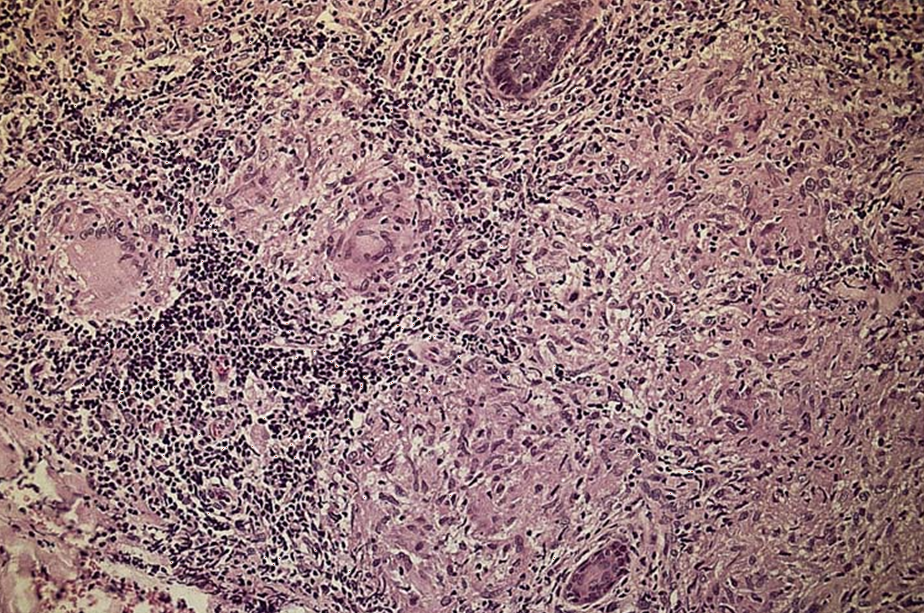

What is shown in the pic ?

Granulomas